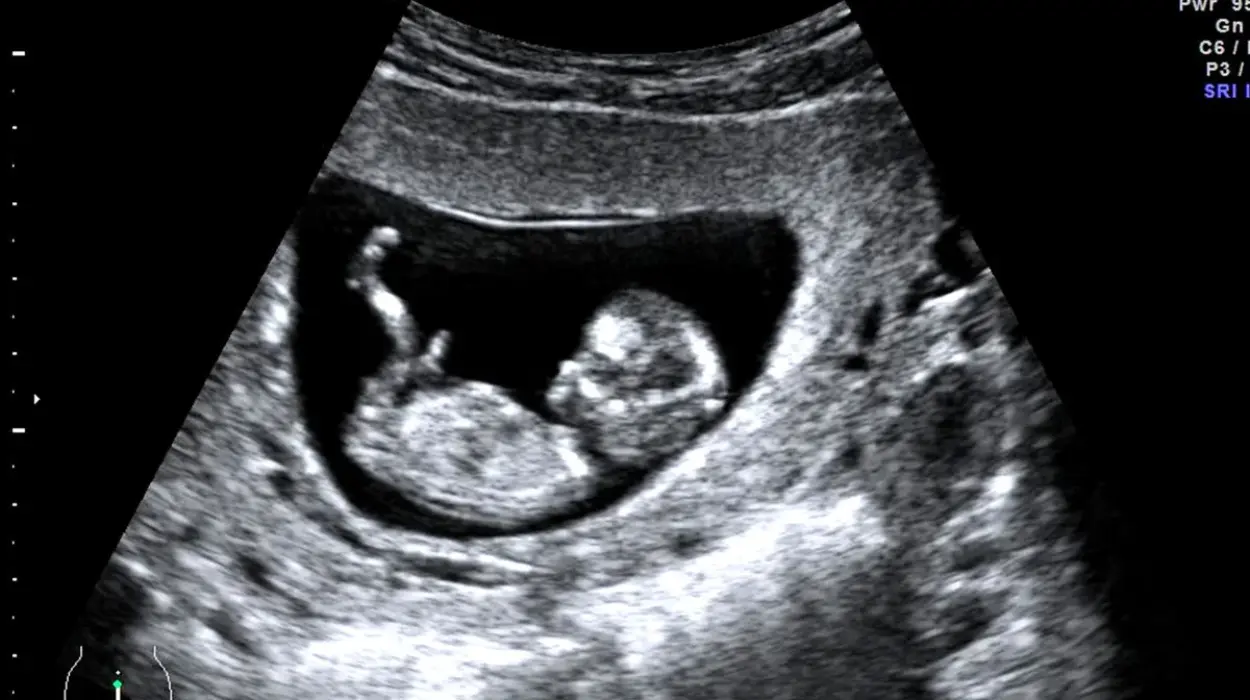

UK (Parliament Politics Magazine) – Experts warn UK’s unregulated pregnancy scan clinics may misdiagnose conditions, give false miscarriage claims, putting mothers and babies at risk.

As reported by The Guardian, health experts warn Britain’s high street pregnancy scan clinics could endanger mothers and babies due to untrained staff.

Experts warn that hospital staff have seen cases of misdiagnoses and missed conditions, including false claims of malformed or deceased babies.

The SoR warns that some private clinics have given false ectopic pregnancy diagnoses, a potentially life-threatening condition. They have also failed to detect actual ectopic pregnancies, cervical problems, and abnormalities in unborn babies.

“One time, we had a lady referred in from a private clinic who was eight or nine weeks pregnant. The sonographer at the private clinic said there was no heartbeat for the baby and that the baby was very, very malformed, and they sent her in for an induced miscarriage.”

“The trust I was working in never accepts reports that come in from private clinics, so we started scanning the lady, who was in tears. On the scan there was clearly a beautiful nine-week pregnancy with a heartbeat. It was absolutely fine.”

“Next to the pregnancy was a blood clot – what they’d done is measured the blood clot. But there was a foetus of normal appearance above it. If the hospital had given her the medication the private clinic had recommended, that baby would have miscarried.”